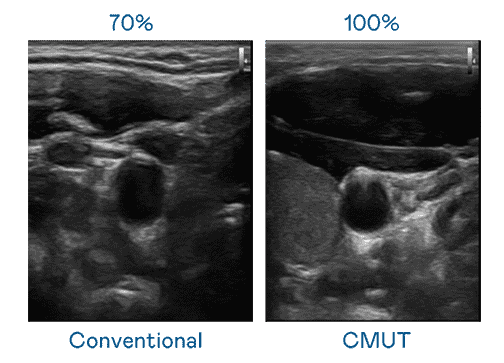

CMUT 技术是一种用电容式微机电元件来产生超音波讯号的技术。。。。与传统 PZT 压电式技术相比,,CMUT 频宽增加 30%,,,,更宽频的超音波讯号让影像解析度大幅提升,,,是实现高影像品质医疗超音波扫描、、、、促进精准医疗发展的关键技术。。

大频宽带来超清晰影像

超音波影像的解析度高低,,,,首先取决于探头能发出的讯号频宽。。。。尊时凯龙 CMUT 可提供高清晰的超音波讯号,,,提供高频宽、、高灵敏度、、、影像纹理细节更高的超音波影像,,,,协助医护人员缩短影像判读时间及利用精准的医疗影像进行诊断。。